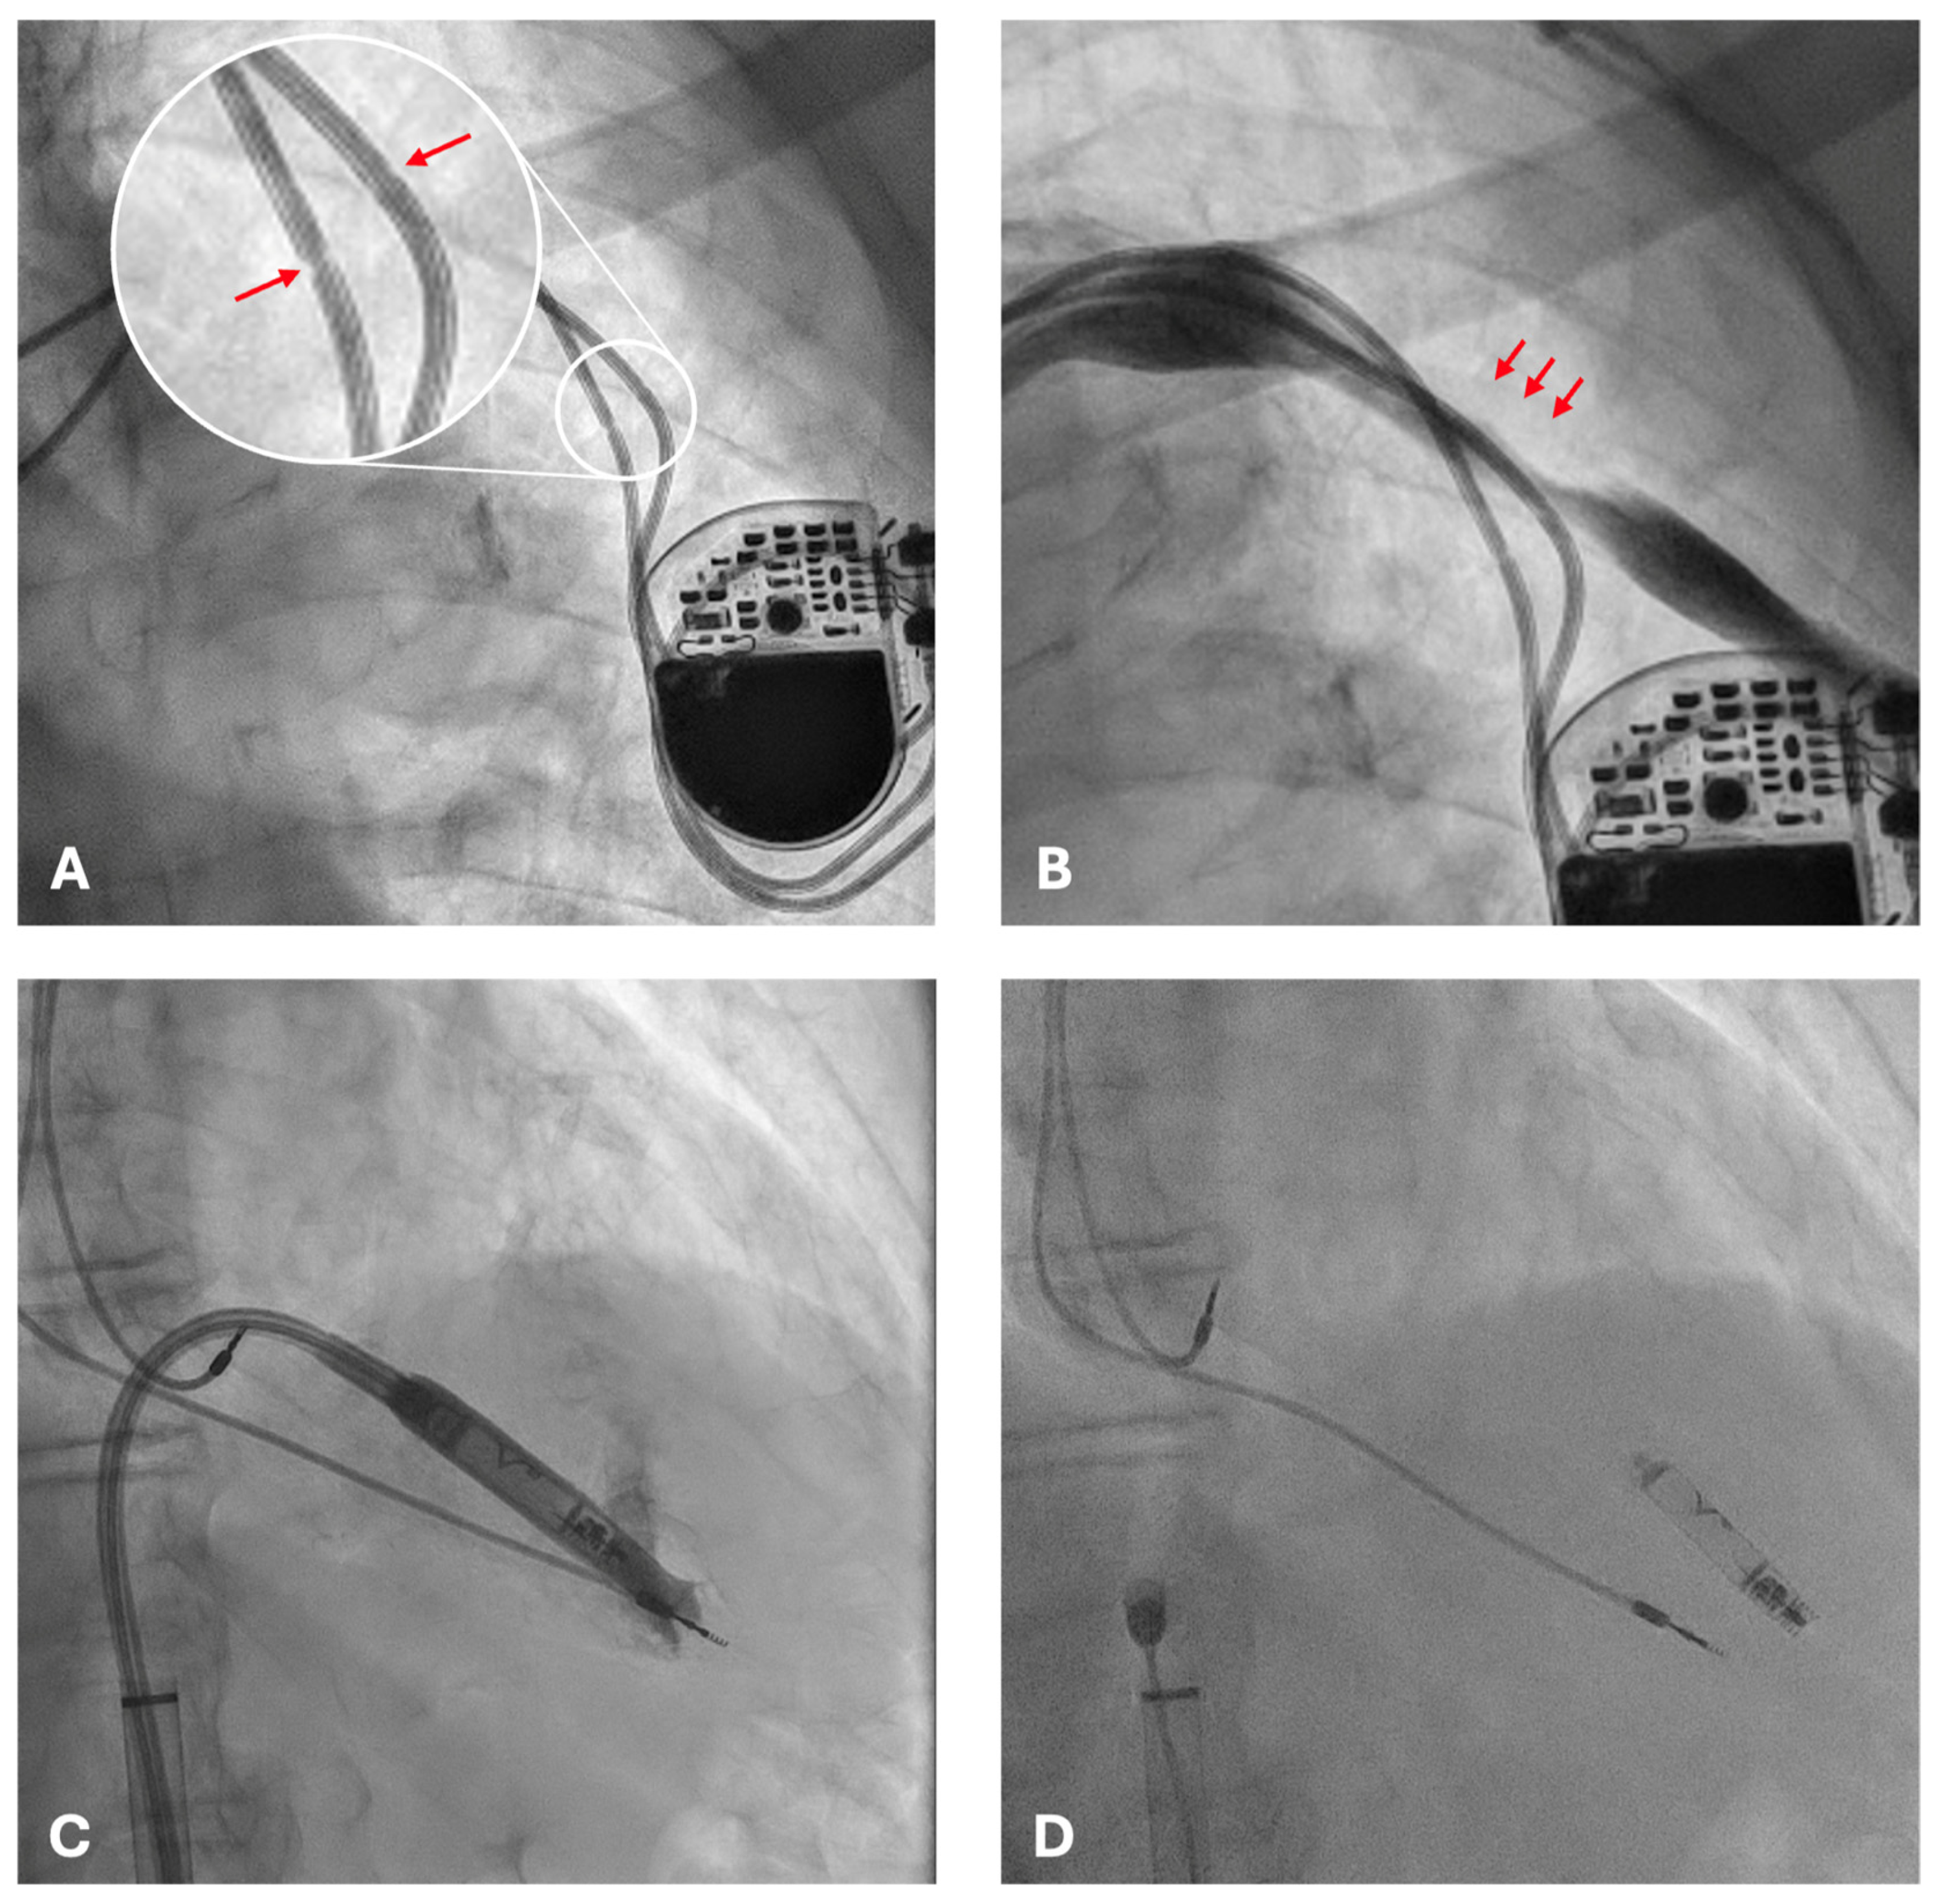

2. Case Presentation